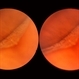

- pars plana, snowbank

- Pars plana snowbank.